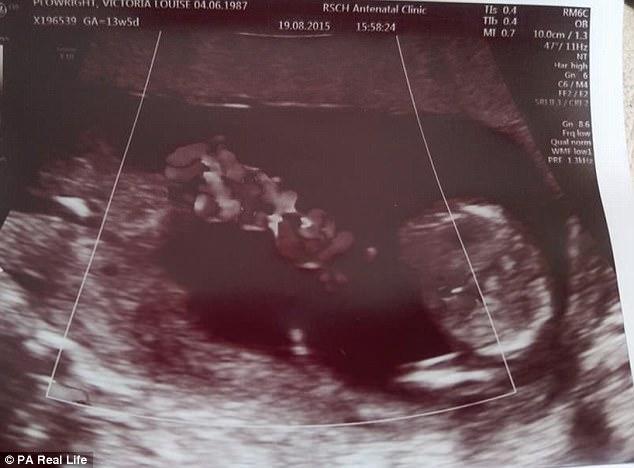

Το υπερηχογράφημα των 10 εβδομάδων έδειξε ότι τα δίδυμα μοιράζονταν τον ίδιο αμνιακό σάκο και η 30χρονη μητέρα, η Vicky Plowright, σοκαρίστηκε όταν έμαθε ότι οι ομφάλιοι λώροι τους θα μπορούσαν να μπερδευτούν μεταξύ τους και να διακόψουν την παροχή οξυγόνου, κάτι που σήμαινε πως θα μπορούσαν να πεθάνουν και τα δύο.

Η Vicky από το Godalming του Surrey της οποίας ο αρραβωνιαστικός είναι ο 32χρονος Chris Cremer, δήλωσε το εξής: “Ήμουν με την αδελφή μου, τη Georgina, και μας είπαν ότι τα δίδυμα ήταν μονοαμνιακά, δηλαδή ότι μοιράζονταν τον ίδιο σάκο.”

Η Vicky είχε πάει για το υπερηχογράφημα των 10 εβδομάδων με τη Georgina, περιμένοντας να είναι μια εξέταση ρουτίνας. Όμως αυτό που έμαθε μετά την εξέταση, πάγωσε το χαμόγελο στα χείλη της.

“Το υπερηχογράφημα έδειχνε ότι τα δίδυμα μας μοιράζονταν τον ίδιο αμνιακό σάκο,” συνέχισε η Vicky. “Είπαν ότι σήμαινε ότι τα μωρά ήταν σε υψηλό κίνδυνο και ότι έπρεπε να επιστρέψουμε το συντομότερο δυνατό για να δούμε έναν ειδικό.”